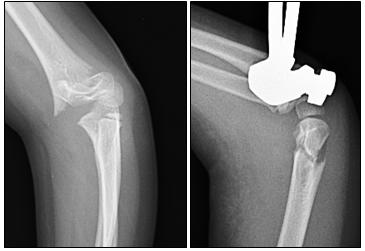

Fratture del femore distale

Sono distacchi epifisari meno frequenti rispetto ad altre sedi ma hanno maggiori conseguenze sull’accrescimento osseo per il potenziale di crescita della cartilagine di accrescimento del femore distale.

Possono quindi essere responsabili di notevoli dismetrie in difetto oltre che di deviazioni assiali.

Trattamento:

- Tipo Salter 1: immobilizzazione gessata;

- Tipo Salter 2: è il più frequente ed in grado di determinare deviazioni assiali in varo-valgo, procurvato-recurvato da sviluppo asimmetrico della cartilagine;

- Tipo Salter 3-4: presentano maggiori problematiche per le difficoltà di una riduzione anatomica (fratture monocondiloidee, bi-condiloidee, frattura triplanare);

- Tipo Salter 5: tipiche dei traumatismi da cruscotto, risultano spesso misconosciute e diagnosticate tardivamente per precoce chiusura della cartilagine di accrescimento.

Molto spesso nei distacchi tipi 1 e 2 al trattamento con gesso si associa una sintesi con fili percutanei. Nei distacchi tipo 3-4 la riduzione deve essere anatomica (oltre 2 mm di scomposizione riduzione cruenta e sintesi a cielo aperto). Torna su